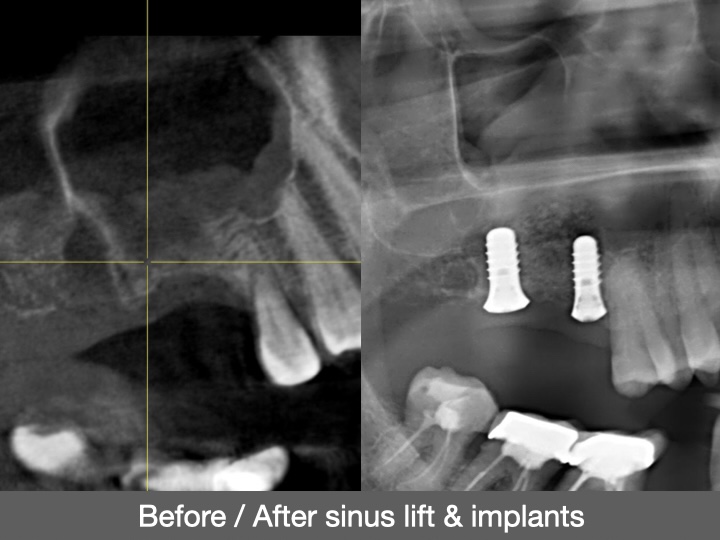

Lorsque le volume osseux a diminué à la suite d’une perte dentaire ou d’une maladie parodontale, l’élévation sinusienne consiste à déplacer le plancher du sinus afin de créer un espace destiné à recevoir un matériau de greffe osseuse. Cette procédure vise à soutenir une hauteur osseuse suffisante, pouvant être prise en compte lors de l’évaluation des options restauratrices.

En contribuant à l’augmentation du volume osseux du maxillaire supérieur, l’élévation sinusienne participe à la planification de traitements restaurateurs, avec une attention portée à la fonction et au soutien des structures dentaires.